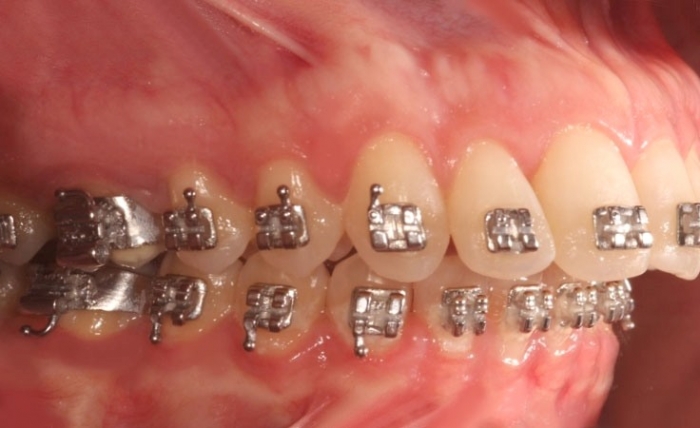

Mordida inicial